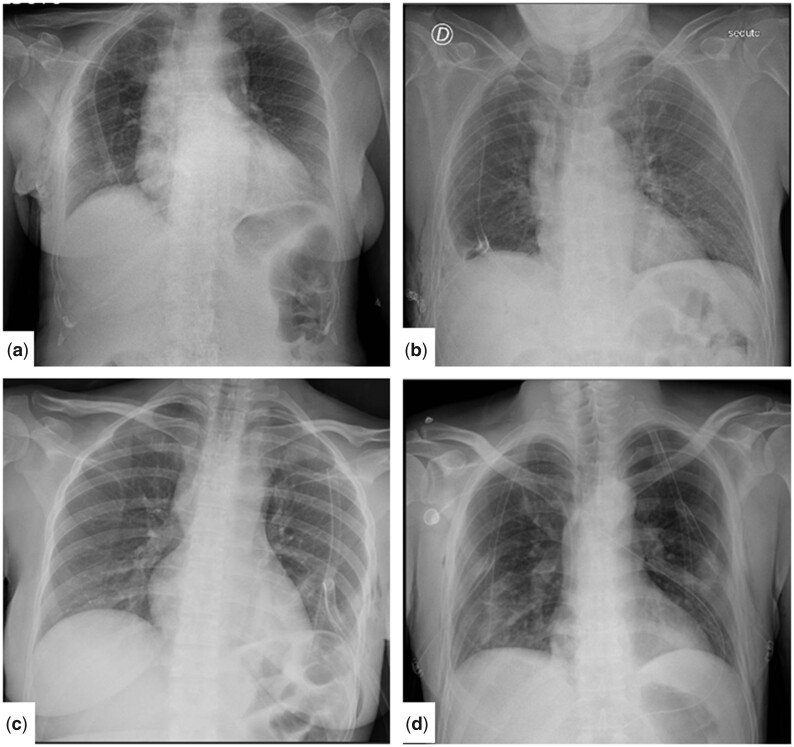

Figure 3:

Example of T-tube kinking on chest X-ray (highlighted with dotted line).

In addition, the risk of kinking was significantly reduced in T-tube group. We explained this finding with the easier positioning set and the absence of angulations required compared to J-shape tube. Indeed, the T-tube is already preformed and, once having occupied the mid-hemithorax position, maintains by itself diametrically opposed extremities. In the rare event of T-tube kinking, due to its displacement following pulmonary re-expansion (Fig. 3), the drainage remained functional in almost all these occasions.